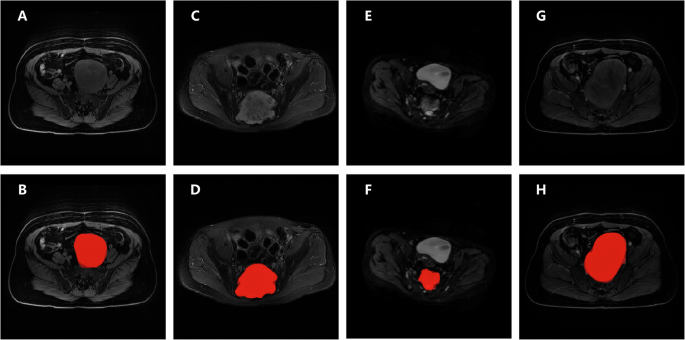

The average Dice score and IoU value of the segmentation model were 0.758 and 0.610, respectively. For T1-w, T2-w, DWI, and CET1-w sequences, Dice scores were 0.606, 0.792, 0.694, and 0.728, and IoU values were 0.472, 0.678, 0.573, and 0.598, respectively. As shown in Fig. 1, the segmentation model achieved a relatively good segmentation effect.

A, B T1-w images of a 62-year-old female patient with neurofibroma; C, D T2-w images of a 44-year-old male patient with mucinous papillary ependymoma; E, F DWI images of a 45-year-old female patient with schwannoma; G, H CET1-w images of the same patient as (A) and (B). The second line shows T1-w, T2-w, DWI and CET1-w images (from left to right) with model’s segmentation and radiologist’s segmentation, darker color represents radiologist’s segmentation.